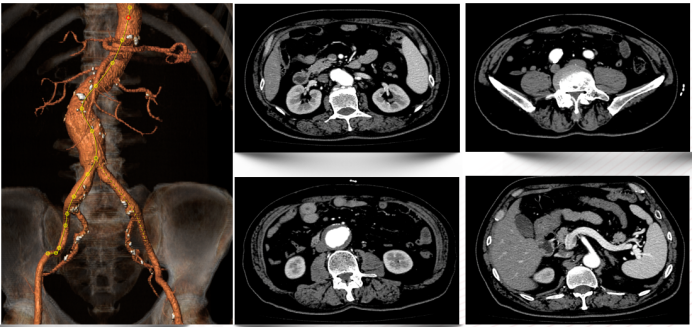

患者男,73岁,因“发现腹主动脉瘤3年余”入院。既往高血压、糖尿病史,长期吸烟。术前CTA显示肾下腹主动脉瘤,近端瘤颈充足,左侧髂内动脉狭窄,右侧正常。

★ 病例2:右髂外动脉闭塞,保留左侧通畅髂内动脉

患者女,66岁,腹主动脉瘤合并右髂外动脉闭塞。术中开通右侧髂外动脉,封堵右侧髂内动脉,保留左侧通畅髂内动脉。

回顾分析了2013年1月至2022年7月接受EVAR并处理髂内动脉的患者,按血供保留方式分为三组:单侧髂内动脉血供组(单侧血供组,UP)、保留双侧髂内动脉血供组(双侧血供组,BP)和未保留髂内动脉血供组(无血供组,BE)。

结果提示:

双侧髂内动脉栓塞组高龄、双侧髂总动脉瘤、髂内动脉瘤的比例高于单侧或双侧髂内动脉保留组。

三组围术期并发症、死亡率、再干预率无显著差异。

3年以上随访结果显示双侧栓塞组的臀肌跛行发生率显著高于其它两组,而肠缺血发生率虽高于其它两组,但无统计学差异。